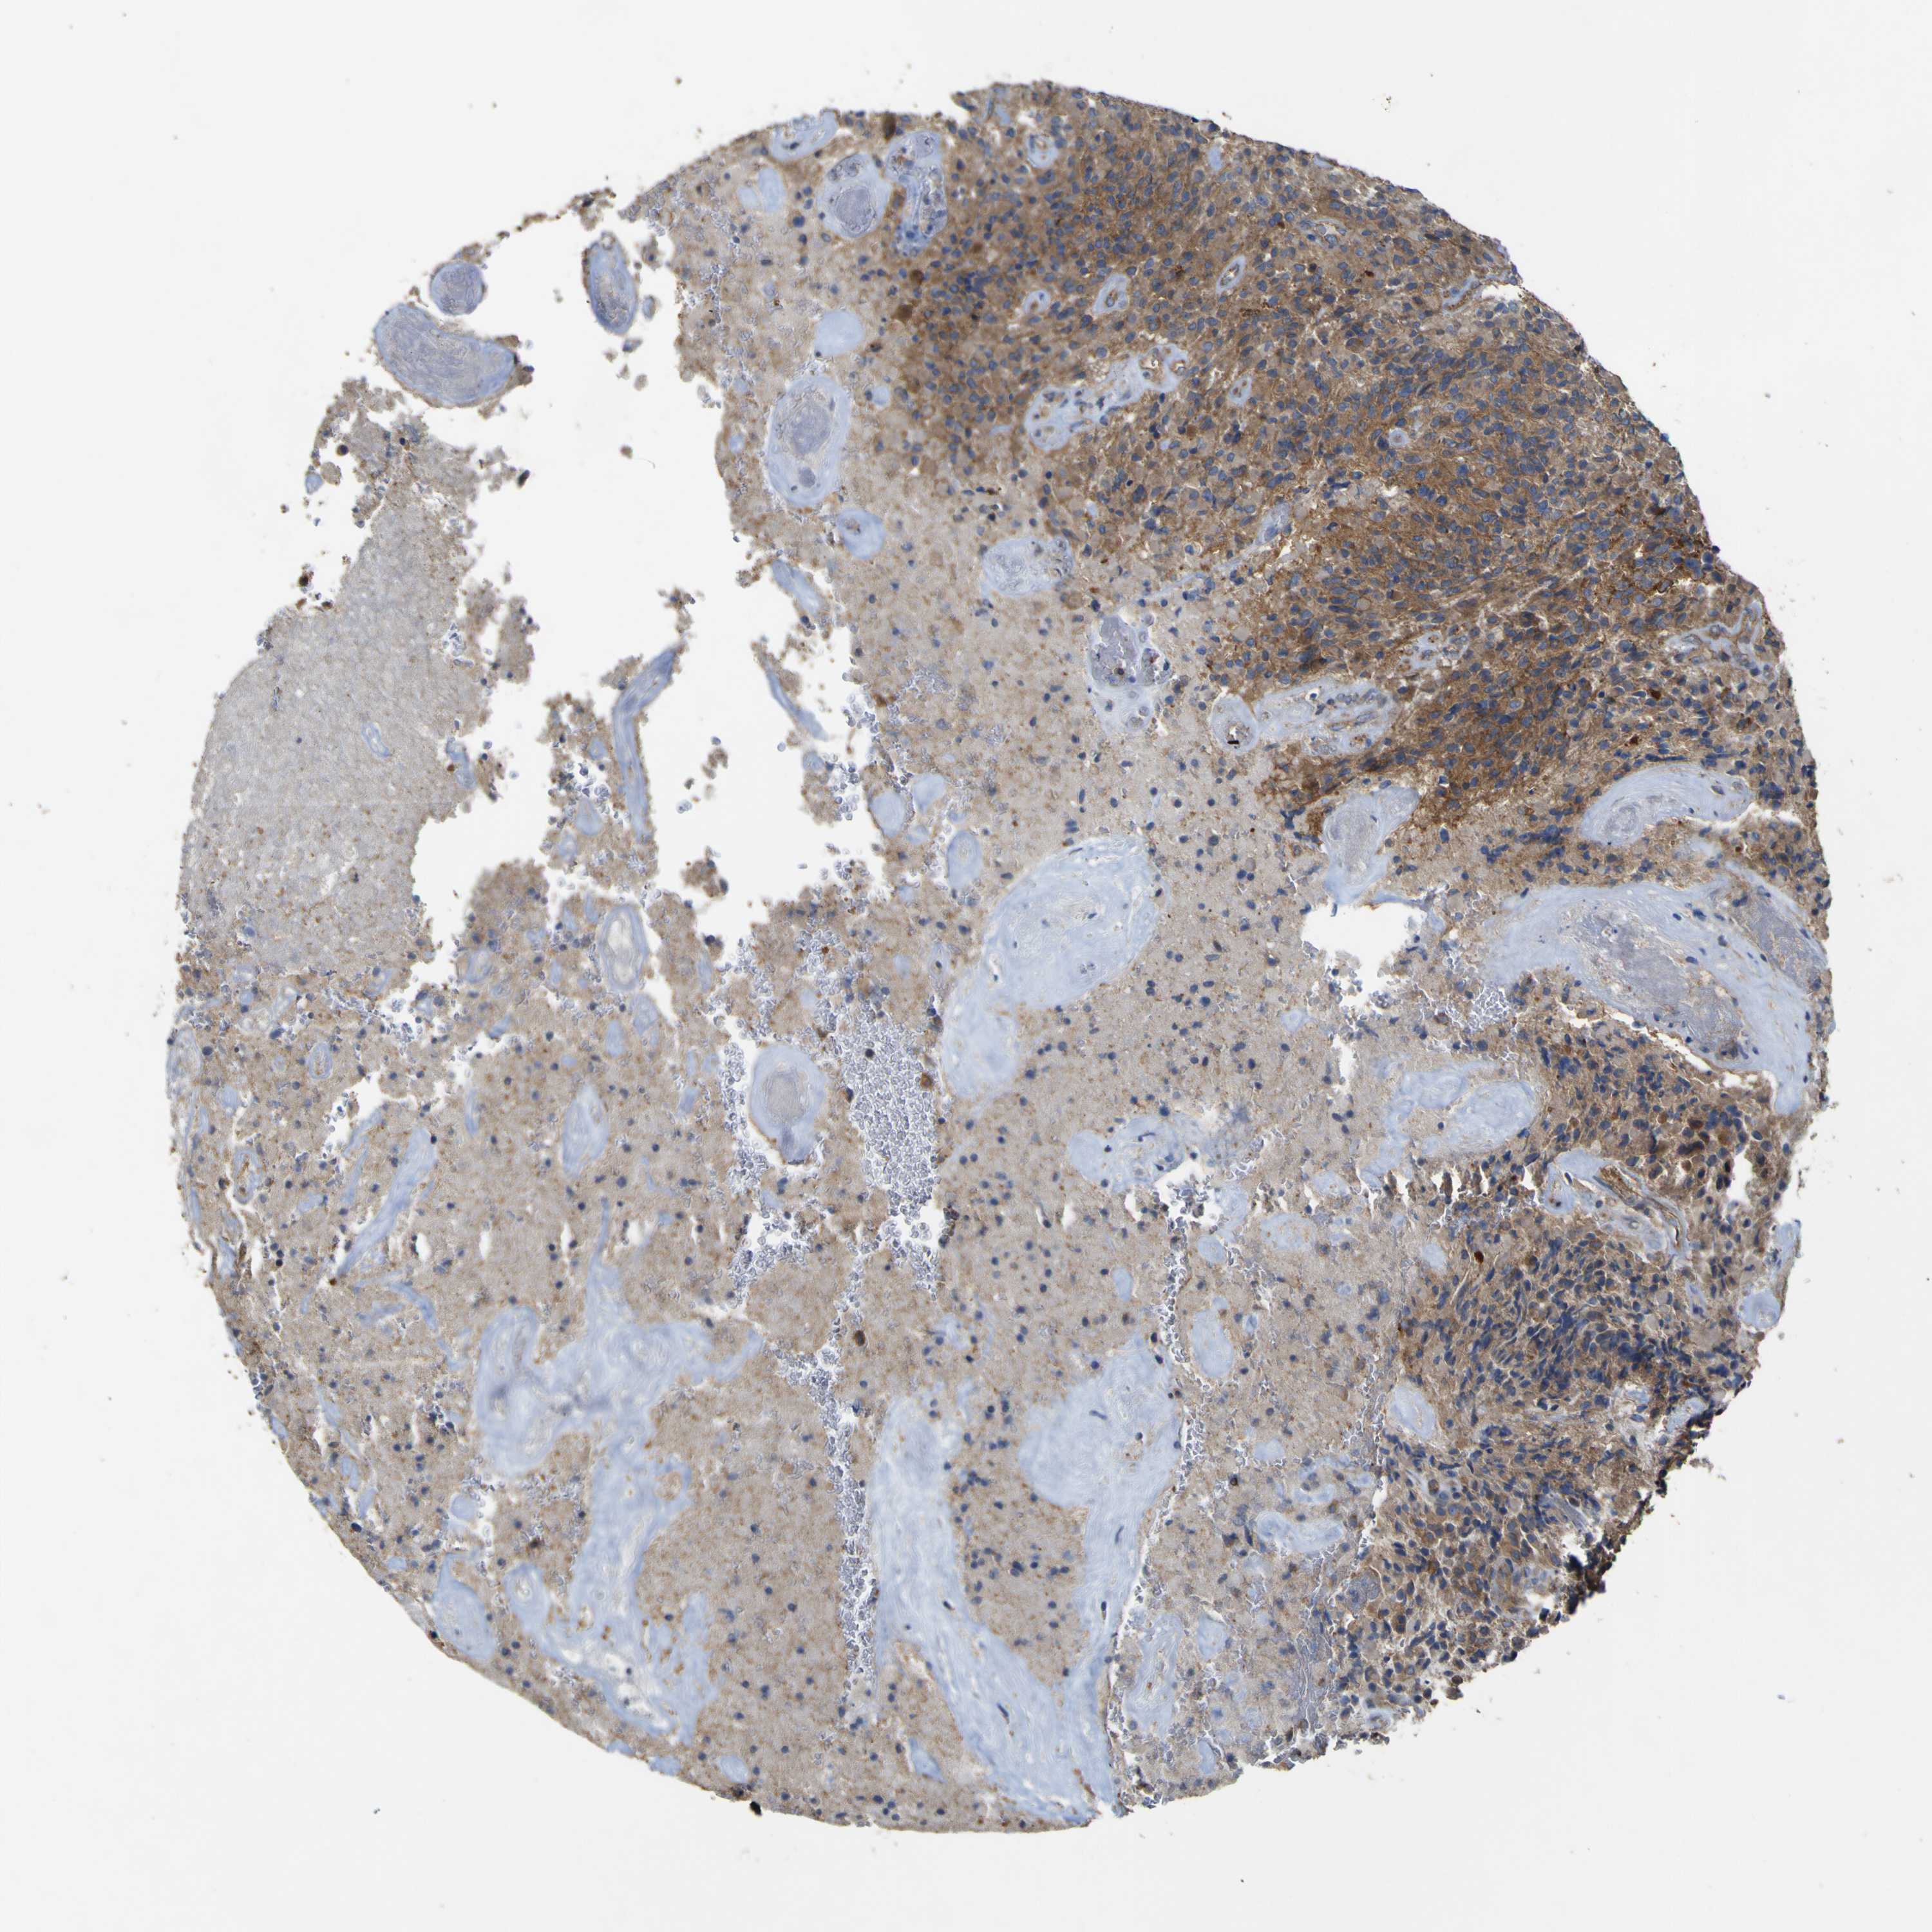

GLIOMA - Protein expressioni

A mouse-over function shows sample information and annotation data. Click on an image to view it in a full screen mode. Samples can be filtered based on level of antibody staining by selecting one or several of the following categories: high, medium, low and not detected. The assay and annotation is described here.

Note that samples used for immunohistochemistry by the Human Protein Atlas do not correspond to samples in the TCGA dataset.

Antibody stainingi

Antibody staining in the annotated cell types in the current human tissue is reported as not detected, low, medium, or high, based on conventional immunohistochemistry profiling in selected tissues. This score is based on the combination of the staining intensity and fraction of stained cells.

Each image is clickable and will lead to virtual microscopy that enables deeper exploration of all samples and also displays staining intensity scores, fraction scores and subcellular localization as well as patient and tissue information for each sample.

Antibody HPA012948

Staining

High

Medium

Low

Not detected

Intensity

Strong

Moderate

Weak

Negative

Quantity

>75%

75%-25%

<25%

None

Location

Nuclear

Cytoplasmic/membranous

Cytoplasmic/membranous,nuclear

Glioma, malignant, High grade

Glioma, malignant, Low grade